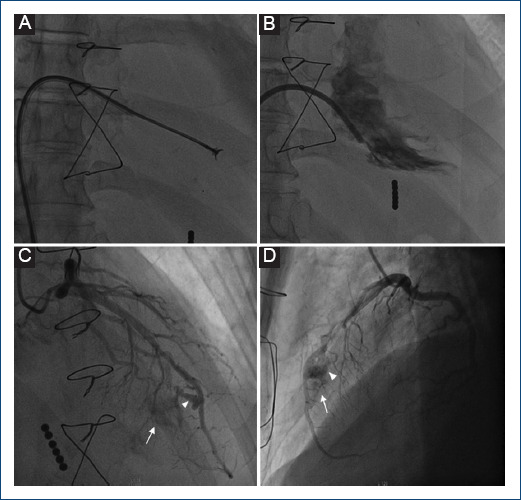

[Aneurysms and coronary artery fistula after endomyocardial biopsy in a patient with a heart transplant. Angiographic and clinical evolution. Report of a case.]

{"title":"[Aneurysms and coronary artery fistula after endomyocardial biopsy in a patient with a heart transplant. Angiographic and clinical evolution. Report of a case.]","authors":"Pedro D Díaz-Sarasa, Herón G Méndez-Sánchez, Guering Eid-Lidt","doi":"10.24875/ACM.24000036","DOIUrl":null,"url":null,"abstract":"","PeriodicalId":93885,"journal":{"name":"Archivos de cardiologia de Mexico","volume":" ","pages":"111-114"},"PeriodicalIF":0.0000,"publicationDate":"2024-07-09","publicationTypes":"Journal Article","fieldsOfStudy":null,"isOpenAccess":false,"openAccessPdf":"https://www.ncbi.nlm.nih.gov/pmc/articles/PMC12148514/pdf/","citationCount":"0","resultStr":null,"platform":"Semanticscholar","paperid":null,"PeriodicalName":"Archivos de cardiologia de Mexico","FirstCategoryId":"1085","ListUrlMain":"https://doi.org/10.24875/ACM.24000036","RegionNum":0,"RegionCategory":null,"ArticlePicture":[],"TitleCN":null,"AbstractTextCN":null,"PMCID":null,"EPubDate":"","PubModel":"","JCR":"","JCRName":"","Score":null,"Total":0}